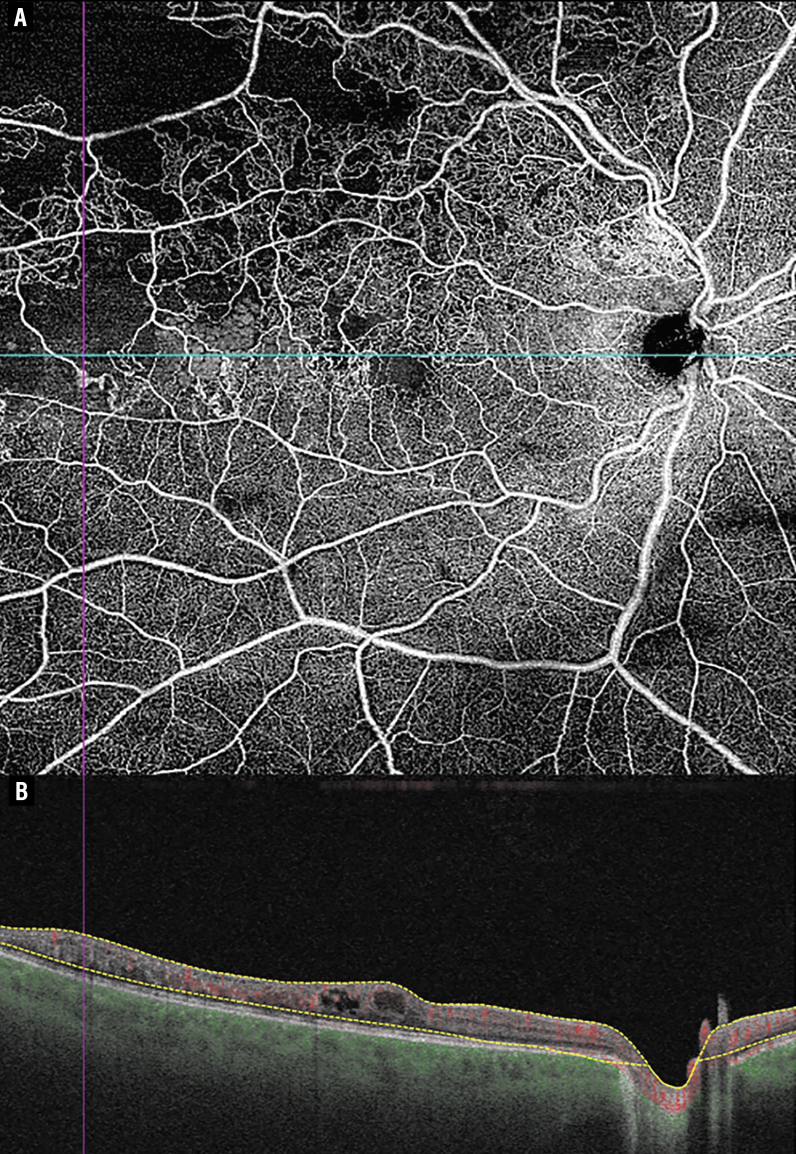

| Figure 1. Right eye with branch retinal vein occlusion, imaged using expanded-field SS-OCTA (Zeiss PLEX Elite 9000) during routine follow-up. (A) 12 × 12 mm SS-OCTA image acquired at 100 kHz, demonstrating areas of nonperfusion (pink and blue lines indicate the location of the corresponding B-scan). (B) Corresponding B-scan with vascular overlay; yellow dashed lines represent segmentation boundaries. |

SS-OCTA can efficiently characterize many retinal microvascular metrics including retinal area and length densities, foveal avascular zone area, various flow areas and signal voids in microvascular networks.4 The combination of faster scan speed and increased wavelength offers improved sensitivity roll-off and reduced potential for scattering from the retinal pigment epithelium. Taken together, these factors all contribute to improvements in accuracy. Such improvements are particularly important in evaluating densely vascularized areas such as the optic nerve head, where high precision is necessary to discern structures.4 This higher speed is also helpful in visualizing deeper layers such as the deep capillary plexus and choroid, which are particularly susceptible to sensitivity roll-off.5,6 Furthermore, faster scan speeds lead to reductions in artifacts that may interfere with evaluation.7 These characteristics may afford more accurate grading and characterization of retinal pathology.

These improvements in image acquisition have led to a number of novel applications, especially in clinical settings. This technology has been applied to detecting changes in CC perfusion among eyes with varying levels of AMD, and there is substantial potential for further evaluation of this relationship.2,11 SS-OCTA has also demonstrated utility in both the early diagnosis and management of diabetic retinopathy. Compared to SD-OCT, SS-OCTA has superior visualization of the vitreoretinal interface, utility in convenient evaluation of non-perfusion area12 and improved early detection of retinal microvasculature alterations and CC abnormalities.10 Other applications of SS-OCTA have included characterizing areas of nonperfusion in eyes with ischemic retinal vein occlusion10 and evaluating vessel density alterations associated with visual function changes in eyes with retinal artery occlusion.13